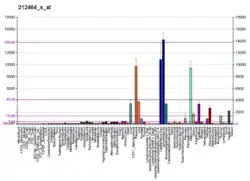

- ↑ Chicco D, Alameer A, Rahmati S, Jurman G (November 3, 2022). "Towards a potential pan-cancer prognostic signature for gene expression based on probesets and ensemble machine learning". BioData Mining. 15 (1): 28. doi:10.1186/s13040-022-00312-y. eISSN 1756-0381. PMC 9632055. PMID 36329531.